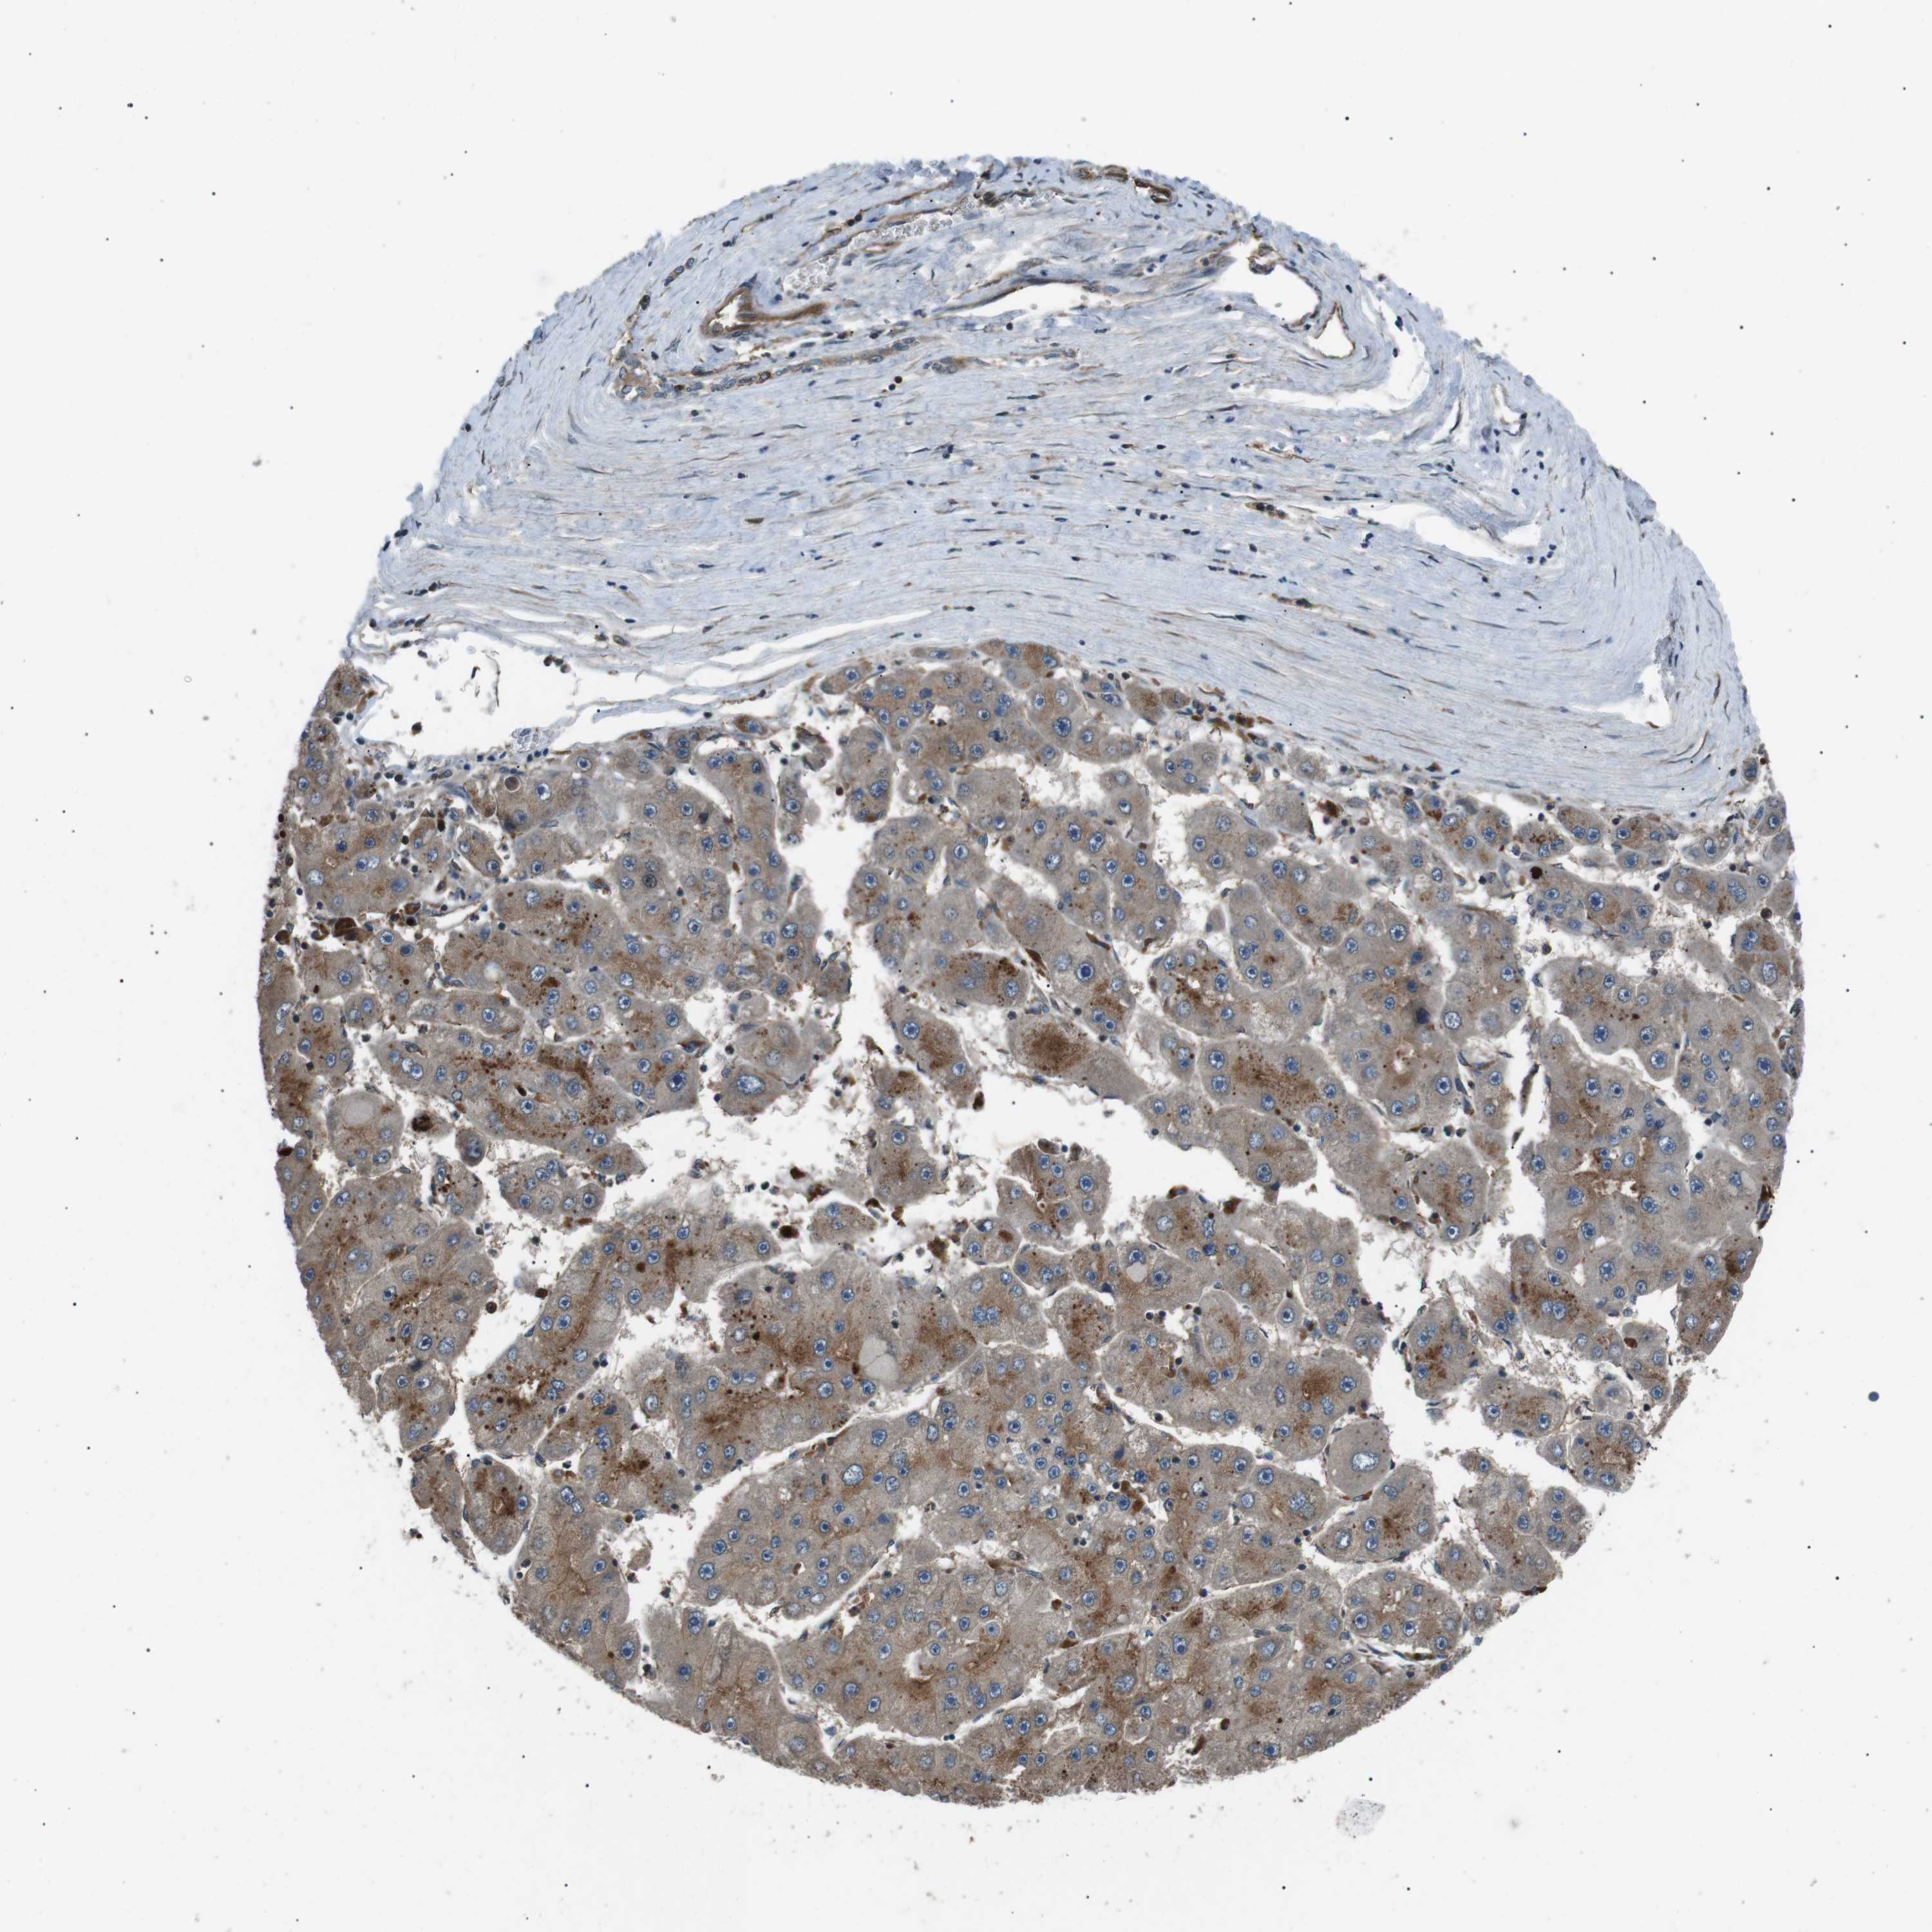

LIVER CANCER - Protein expressioni

A mouse-over function shows sample information and annotation data. Click on an image to view it in a full screen mode. Samples can be filtered based on level of antibody staining by selecting one or several of the following categories: high, medium, low and not detected. The assay and annotation is described here.

Note that samples used for immunohistochemistry by the Human Protein Atlas do not correspond to samples in the TCGA dataset.

Antibody stainingi

Antibody staining in the annotated cell types in the current human tissue is reported as not detected, low, medium, or high, based on conventional immunohistochemistry profiling in selected tissues. This score is based on the combination of the staining intensity and fraction of stained cells.

Each image is clickable and will lead to virtual microscopy that enables deeper exploration of all samples and also displays staining intensity scores, fraction scores and subcellular localization as well as patient and tissue information for each sample.

Antibody HPA015576

Staining

High

Medium

Low

Not detected

Intensity

Strong

Moderate

Weak

Negative

Quantity

>75%

75%-25%

<25%

None

Location

Nuclear

Cytoplasmic/membranous

Cytoplasmic/membranous,nuclear

Cholangiocarcinoma

Carcinoma, Hepatocellular, NOS